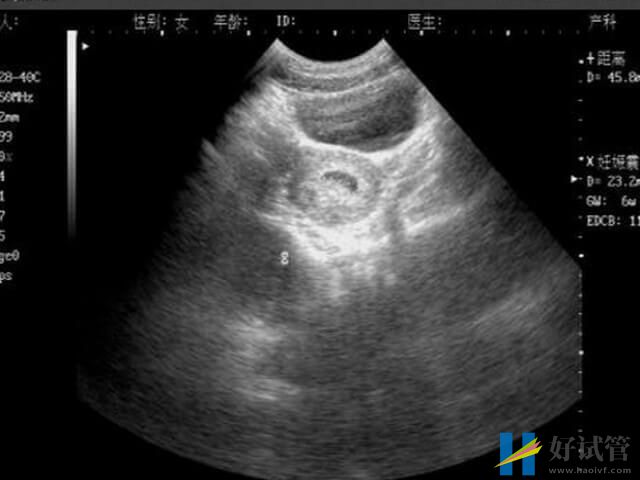

胎停在临床中称为胚胎停育,是指由于某种原因导致的胚胎停止发育,可进一步引起胚胎死亡。一般来说,胎停的发生概率最好的阶段就是怀孕早期的时候,其原因大致就如下所列: